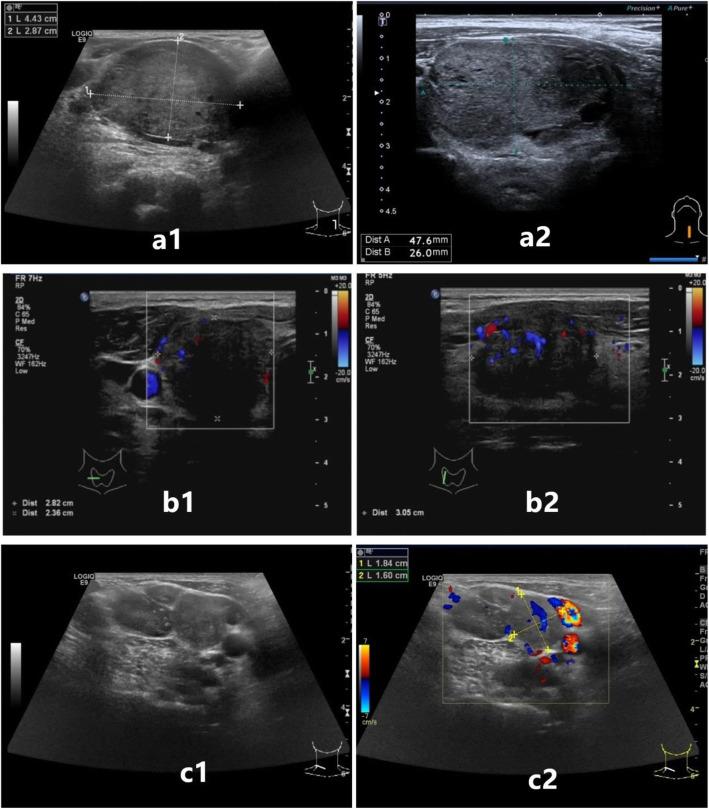

甲状腺髓样癌术前超声特征与术后复发的相关性。

Correlation between preoperative ultrasonic features of medullary thyroid carcinoma and postoperative recurrence.

To investigate the factors that affect postoperative recurrence in medullary thyroid carcinoma (MTC) patients, including preoperative ultrasonic characteristics and other factors.

RESULTS

Single factor Kaplan-Meier (K-M) analysis showed that: ① Preoperative ultrasonic characteristics including tumor size > 40.0 mm, capsular invasion, and metastatic cervical lymph nodes, as well as preoperative calcitonin level > 565.8 pg/ml, and postoperative calcitonin (within one week) level > 45.0 pg/ml were positively correlated with the risk of postoperative recurrence of MTC (P < 0.05); ② There was no evidence to show that sex and age had a statistically significant effect on postoperative recurrence of MTC (P > 0.05). Multivariate Cox regression analysis showed that metastatic lymph nodes shown by ultrasound (HR = 5.368, 95%CI 1.063-27.104, P = 0.042) was an independent risk factor for postoperative recurrence of MTC.

CONCLUSIONS

MTC patients with metastatic lymph nodes shown by ultrasound are prone to postoperative recurrence of MTC. In addition, MTC patients with a tumor > 40.0 mm, capsular invasion, preoperative calcitonin level > 565.8 pg/ml, and postoperative calcitonin level > 45.0 pg/ml are more likely to have postoperative recurrence.